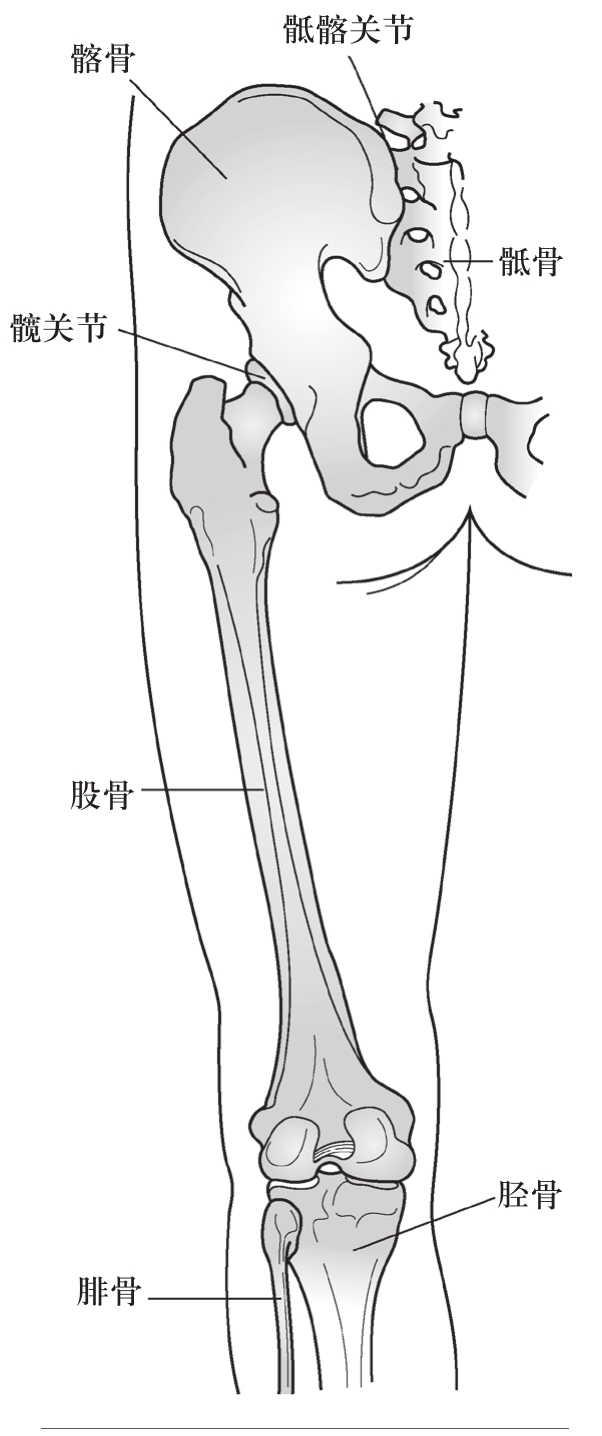

关节位于股骨头与骨盆髋臼的交会处(图2.16)。除了其骨性结构之外,髋关节由许多肌肉与一个网状的韧带提供稳定,这些韧带与肌肉从周围包覆髋关节,为髋关节提供各种力量与稳定度,使其能在各个平面上做各种动作(表2.4)。

图2.16 髋关节

髋关节牵涉到3个平面的动作:

· 矢状面的屈曲与伸直

· 额状面/冠状面的外展与内收

· 水平面的外旋与内旋

· 所有平面上的环绕

髋关节的基本动作范围,由邻近之膝盖与骨盆的关节位置以及肌肉长度而定。在直立的解剖学姿势中,基准的范围如下(Norkin & Levangie,1993):

· 屈曲(膝关节屈曲时):110°

· 伸直:30°

· 外展:50°

· 内收:30°

· 外旋:60°

· 内旋:40°

髋关节外旋的基准范围为60°,较内旋的40°更大。在坐位时,髋关节会屈曲,髋关节旋转的角度也会较大,因为此时的关节囊与韧带较为松弛。作用于髋关节的拮抗肌群必须先达到功能性的平衡,才能让(位于下方的)下肢与(位于上方的)骨盆维持在正常的位置。